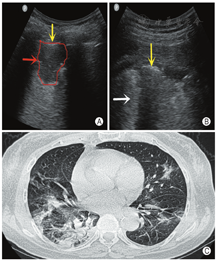

病例1.男,77岁,因"反复发热2周"入院。体温波动于37~38.5 ℃,以下午及夜间明显。入院后行胸部CT检查提示:双肺炎症,病毒性肺炎不能除外。既往有高血压病史30余年;10年前行胆囊切除术、下肢静脉曲张手术;3年前行前列腺癌手术。近2周无武汉疫区居留史,未接触武汉返乡人员(本病例由川北医学院附属医院提供,图12)。

病例2:女,63岁,因"咳嗽、发热、畏寒4天"入院,体温最高39℃。CT:双肺多叶段散在斑片状磨玻璃影,以右肺下叶为主,双侧胸膜增厚。既往有"高血脂"、"甲状腺功能减退",17年前行"子宫全切术"。出生并久居武汉,2020年1月18日到成都旅游,之前未接触类似发热患者(本病例由成都市公共卫生医疗中心提供,图13)。

病例3:男,50岁,因"尿少2年,心累、气促1月、发热、咳嗽2天"入院,体温最高38.5 ℃。2020年1月15日院外胸部CT示:双肺散在模糊小结节,双肺下叶感染,双侧胸腔少量积液;2020年1月2日院外复查CT示:双肺感染灶明显进展,呈散在结节斑片影,部分结节内可见空洞,空洞内可见内容物;2020年2月4日复查CT:双肺散在斑片、磨玻璃、点结、纤维条影,密度不均,边界模糊,双侧胸腔少量积液,心包腔少量积液。既往有"肾功能不全尿毒症期""高血压病3级""2型糖尿病"等。1月前因慢性肾功能衰竭在武汉某三甲医院ICU住院治疗17天,于2020年1月13日到成都某医院因重症肺炎、病毒性肺炎、慢性肾病住院治疗8天后,以"新型冠状病毒肺炎疑似患者"到定点医院隔离治疗,后核酸检测阳性确诊(本病例由成都市公共卫生医疗中心提供,图14)。